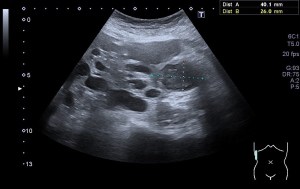

La radiografía revela aumento de las partes y se refrenda en la ecografía como puedes ver en la imagen aunque aún no hay afectación en el hueso en el caso que te presento hoy.

Ecografícamente y debido a su levedad, en el caso de hoy solo observamos cambios en las partes blandas de la cara lateral de la cabeza del quinto metatarsiano, este tejido se muestra heterogéneo, la cortical del hueso ligeramente prominente sin afectación de la misma.